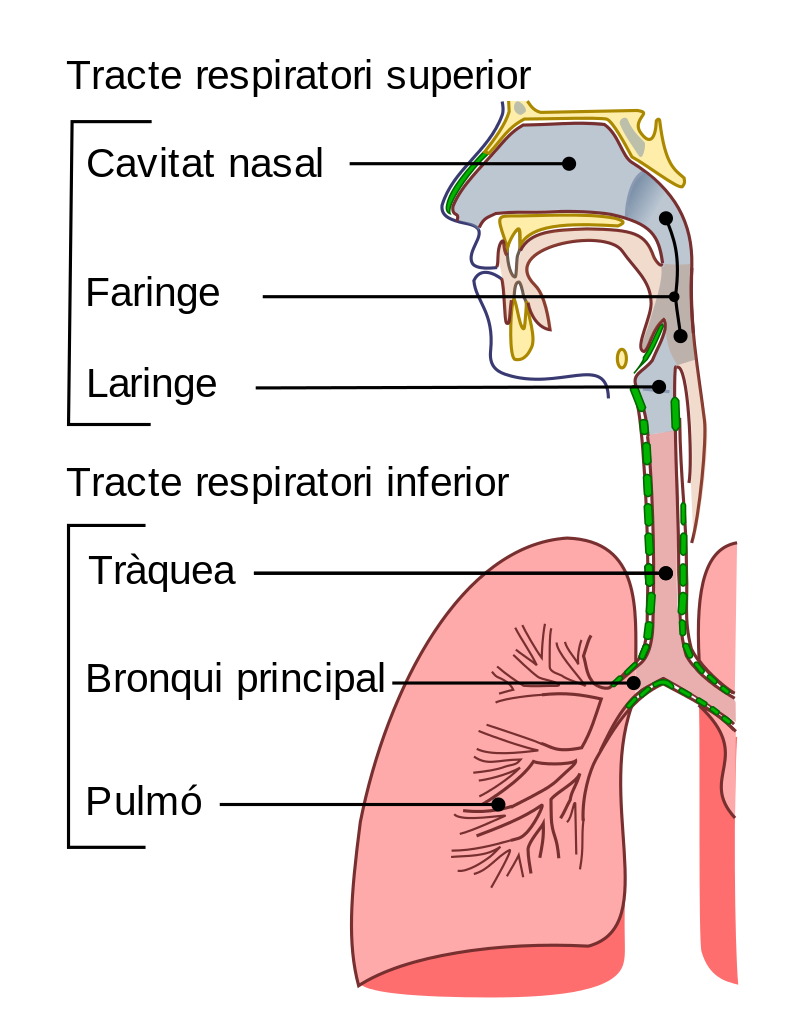

En els humans, l’anatomia d’un sistema respiratori típic és el tracte respiratori (vegeu la figura). El tracte es divideix en dos trams:

- Un tracte respiratori superior: inclou el nas, les cavitats nasals, els sins, la faringe i la part de la laringe per sobre dels plecs vocals.

- Un tracte respiratori inferior: inclou la part inferior de la laringe, la tràquea, els bronquis, els bronquíols i els alvèols.

El tracte respiratori superior pot referir-se a les parts del sistema respiratori sobre l’angle esternal (fora del tòrax), per sobre dels plecs vocals o per sobre del cartílag cricoidal. El tracte consisteix en la cavitat nasal i en els sins paranasals, la faringe (nasofaringe, orofaringe i laringofaringe) i la laringe (vegeu la figura).

El tracte respiratori inferior també s’anomena arbre respiratori o arbre traqueobronquial, per descriure l’estructura ramificadora de les vies respiratòries que subministren aire als pulmons, i inclou la tràquea, els bronquis i els bronquíols (vegeu la figura).